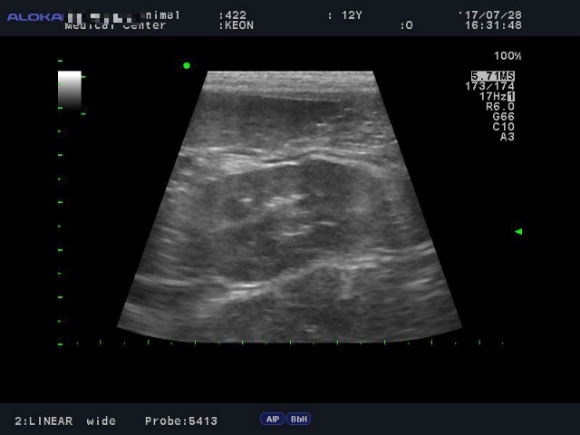

<7월28일> 다시 원점..도로아미타불입니다. 다시봐도 속상하네요 (근데 이게 담낭이 맞긴 한건가..급혼란..)

어제받은 초음파사진들은 몇장 안되니 그냥 다 올려볼게요